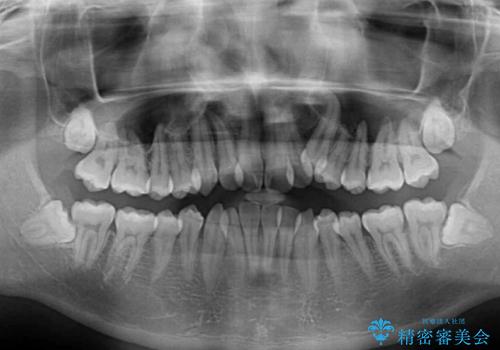

- 上下の八重歯や乱杭歯を気にして来院され患者様です。

スペースを確保するため、上下左右の小臼歯を抜歯し、ワイヤー装置に矯正することとしました。

奥歯の咬み合わせの左右差が大きかったため、変則的な抜歯矯正を行いました。

治療期間はやや長期化しましたが、満足のいく歯並びとなりました。